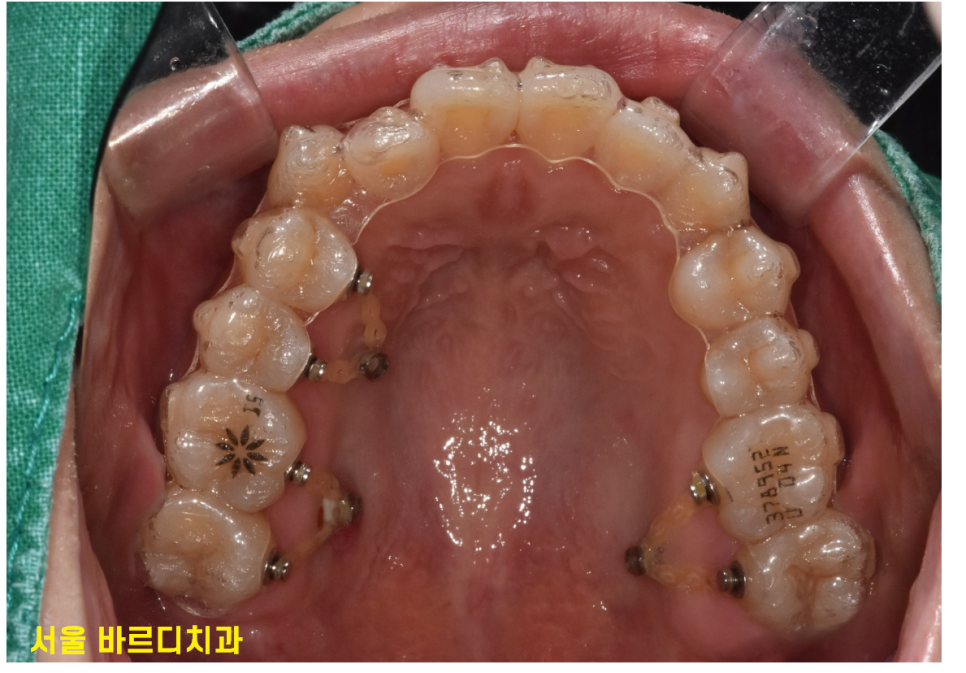

교정 효과를 극대화하기 위해 미니스크류를 심기도 하고

치아에 어태치먼트를 붙이기도 하거든요~~

여기서 치아교정 상식

"어태치먼트란???"

사진을 보면 치아의 겉면에 무언가 붙어있죠~?

치아 이동을 효과적으로 돕기위해 설치한다 보시면 됩니다.

아무리 치아 색상에 맞춰 붙여드려도,,

돌출감이 있기 때문에 티가 납니다.